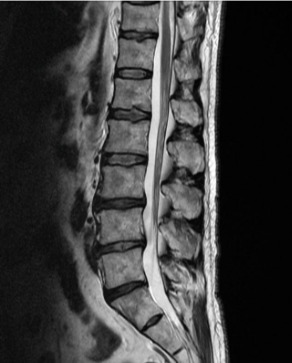

허리디스크를 올바르게 진단할려면 엑스레이로는 힘들며, MRI를 통해 검사해야 올바르게 볼 수 있습니다.

MRI가 몸에 좋지 않지만 허리 통증으로 엑스레이만 진행 할 경우 오진이 많아 계속적인 고통이 계속 된다면 허리디스크를 의심하고 MRI 검사를 한번 받아보시길 권유드립니다.